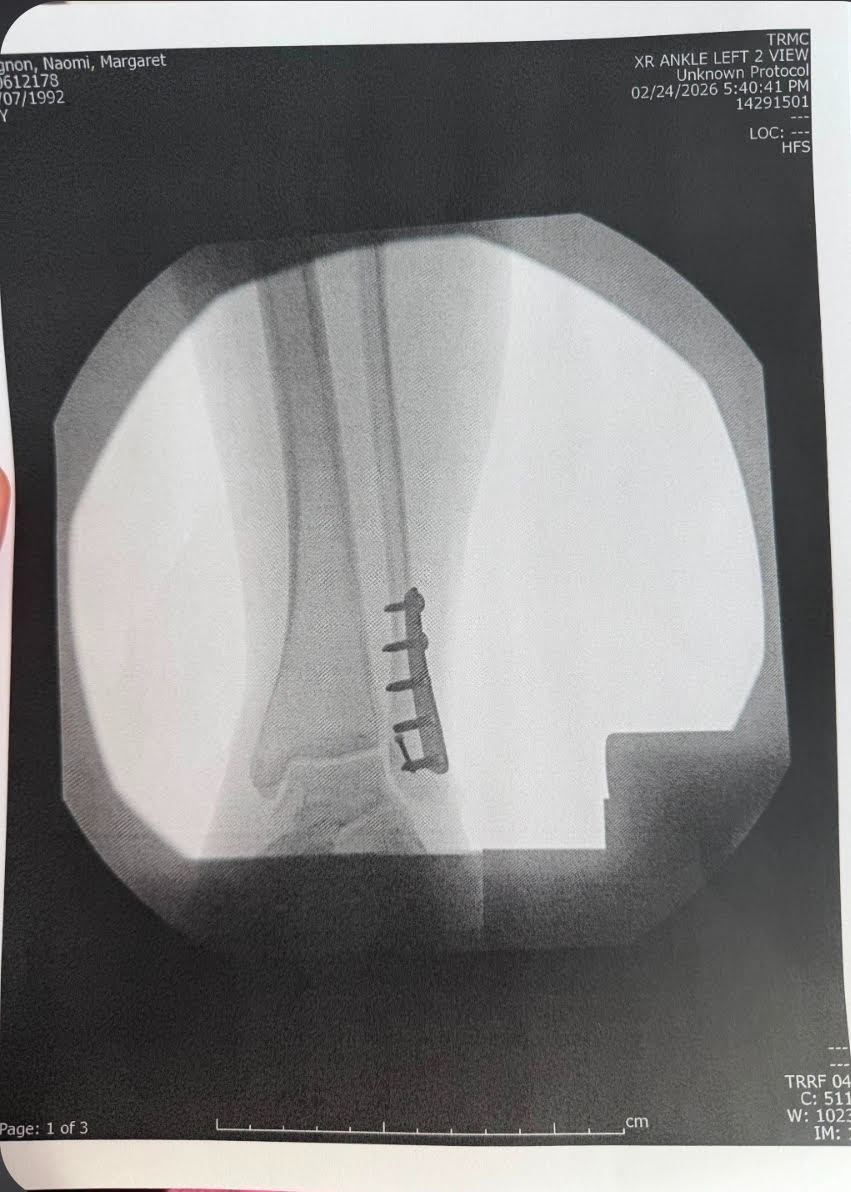

During the first significant snowfall in southern Oregon, Naomi slipped on her front steps and suffered a severe injury—breaking her ankle in multiple places, tearing tendons, and dislocating the joint. She underwent surgery within a week and is now on the long road to recovery. As a mother, it’s heartbreaking to see her in pain and facing so many challenges all at once.